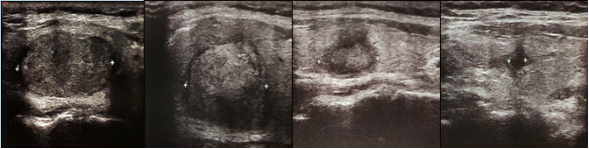

甲状腺结节微波消融病例

术前 术后1个月 术后6个月 术后1年